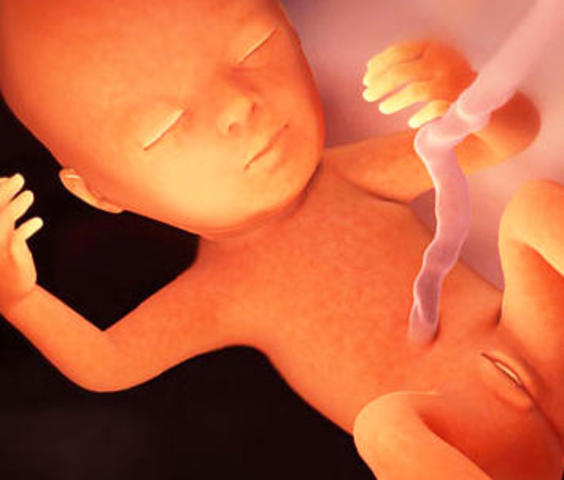

-El embrión pasa a llamarse feto.

-La placenta es el sistema de alimentación del feto.

-Red de finos capilares.

-Filtra sustancias nocivas.

-Primeros movimientos del feto.